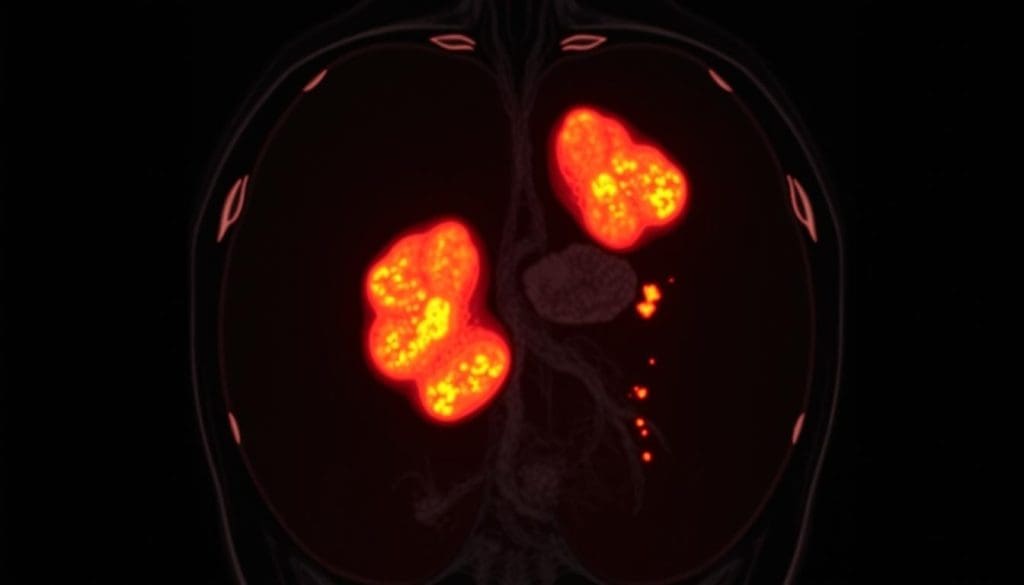

Abnormal lymph nodes on a PET scan often mean lymphoma or cancer. These nodes show up as “hot spots” because they take up more FDG. The uptake level can vary, but in lymphoma, it’s often much higher than normal.

Cancerous Causes of Increased Metabolic Activity

Cancerous lymph nodes light up on PET scans because they work fast. Lymphomas, in particular, make lymph nodes active.

Some common lymphomas that show up on PET scans are:

- Hodgkin lymphoma

- Diffuse large B-cell lymphoma

- Follicular lymphoma